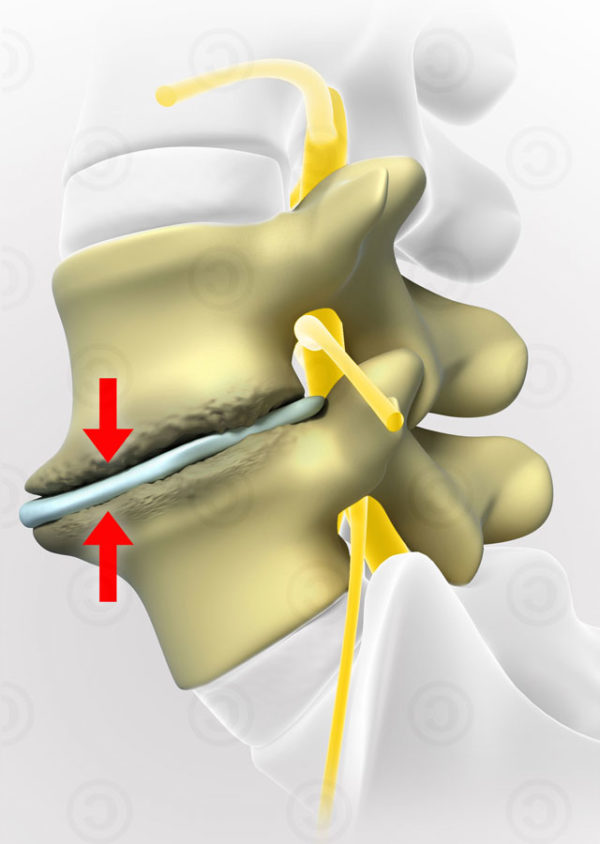

Остеоартрит фасеточных суставов: медицинские снимки и схемы